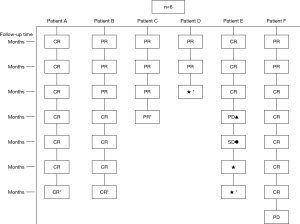

Evaluation of response on tumor

Pulmonary CT was repeated 1, 3, 6, 12, 18 and 24 months after procedure, so as to evaluate local tumor control in the 6 patients after treatment. The results can be seen in Figure 7.

As shown in Figure 7 and Figure 3, there were 2 CRs and 4 PRs after follow-up for 1 month, indicating a response rate (RR) of 6/6, and a disease control rate (DCR) of 6/6; six patients were followed up for 6 months, including one patient who refused follow-up visit (still alive),while the other 5 patients were followed up regularly, including 3 CRs and 2 PRs; five patients were followed up for 12 months, including 3 CRs, 1 PR and 1 PD, indicating an RR of 4/5, a DCR of 4/5, and a progression rate of 1/5; four patients were followed up for 18 months, including 3 CRs and 1 SD, indicating a RR of 3/4 and a DCR of 4/4; four patients were followed up for 24 months, including 1 patient who refused a follow-up visit (still alive), while the other 3 patients were still followed up regularly; there were still 4 patients who were followed up for 30 months, including 1 patient who refused follow-up visit (alive) and 3 patients who were followed up on a regular basis; one patient was followed up for 36 months and had a recurrence of primary lesion, with the response being evaluated as PD. In addition, Figure 7 shows that patient E achieved significant response after implantation of 125I particles, and the response was evaluated as CR 1 month after implantation (Figures 8,9); however, the primary lesion recurred and was enlarged with left lung metastasis in month 12 (Figures 10,11), whereupon the response was evaluated as PD. The patient was given CT-guided implantation of 125I radioactive particles again for treatment of the recurrent lesion. The repeated pulmonary CT after re-implantation showed significant reduction of tumor (reduction rate 27.32%), as shown in Figure 12, and the response was subsequently re-evaluated as SD.